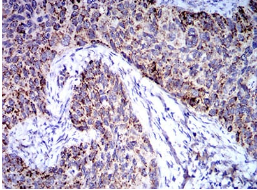

TRIM25 Mouse Monoclonal antibody[5B5B10]

IHC    1/200 - 1/1000